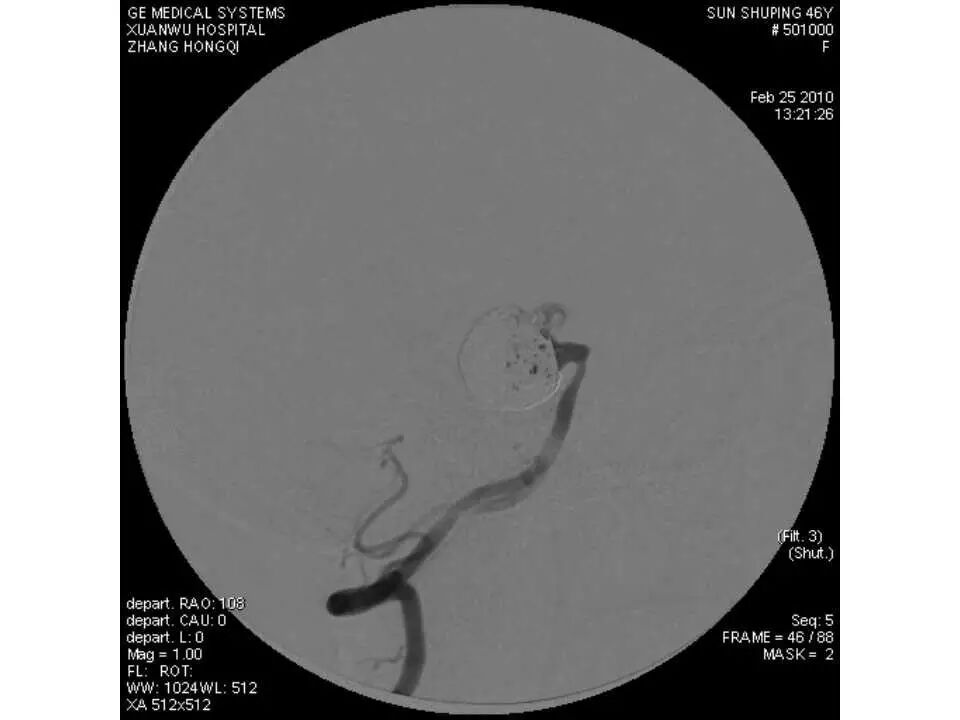

今天为大家分享的是“强生医疗CNV-神经介入专栏”第十五期,由首都医科大学宣武医院何川教授带来的“颅内动脉瘤介入治疗”精彩讲课视频及PPT,欢迎观看、阅读。文章仅代表作者个人观点,如有不同见解,欢迎同道斧正!

何川 ,首都医科大学宣武医院副主任医师,中国医师协会神经介入专业委员会常务委员,长期从事脑血管病和脊髓血管病的手术及介入治疗和相关研究工作。首都医科大学神经外科博士,师从于中国神经介入开创人凌锋教授;日本东北大学医院脑血管病治疗科博士后,师从于日本国脑血管病血管内治疗的开创者高桥教授。